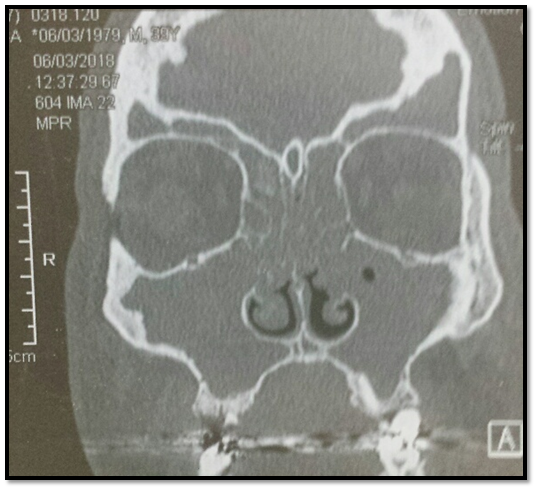

Imagen tomográfica, propiedad de la autora donde se evidencian la totalidad de los senos parasanales con lesiones polipoideas en una rinosinusitis crónica.